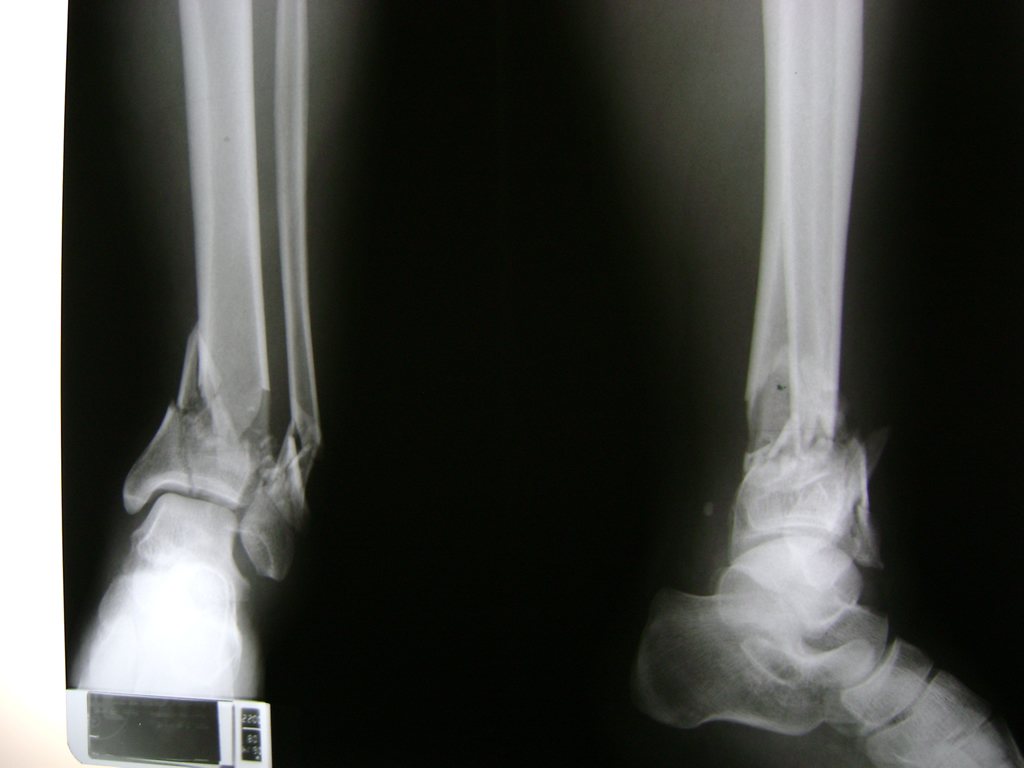

Una fractura de tobillo es la rotura de uno o más de los huesos del tobillo. Estas fracturas pueden ser:

- Parciales (el hueso está sólo parcialmente fisurado, no del todo).

- Completas (el hueso está perforado y está en 2 partes).

- Los extremos de los huesos están desalineados entre sí (desplazados).

- La fractura se extiende hasta la articulación del tobillo (fractura intra-articular).